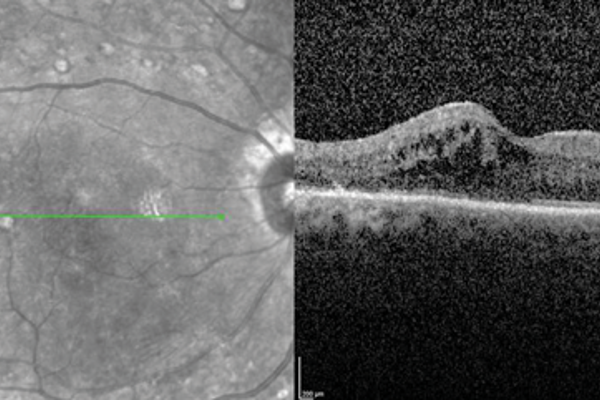

Optical coherence tomography – reinventing the eye examination